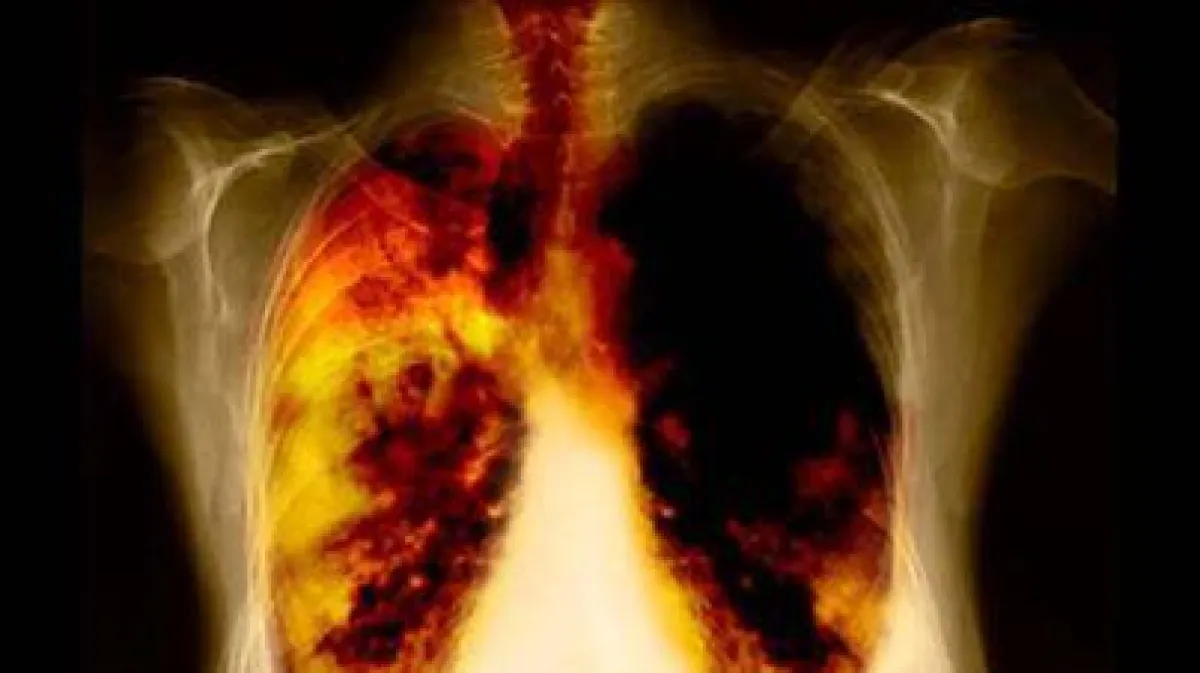

من جهة أخرى يصاب أهالي المناطق البعيدة عن خط الاستواء بسرطان الرئة بصورة أكبر.

وقد توصل العلماء إلى هذه النتيجة بناء على معطيات مصابين بسرطان الرئة من 111 بلدا.بالتالي استنتج المختصون أن فيتامين D لا يعتبر مسؤولاً عن سلامة عظام الإنسان فحسب بل ويكافح السرطان أيضاً.